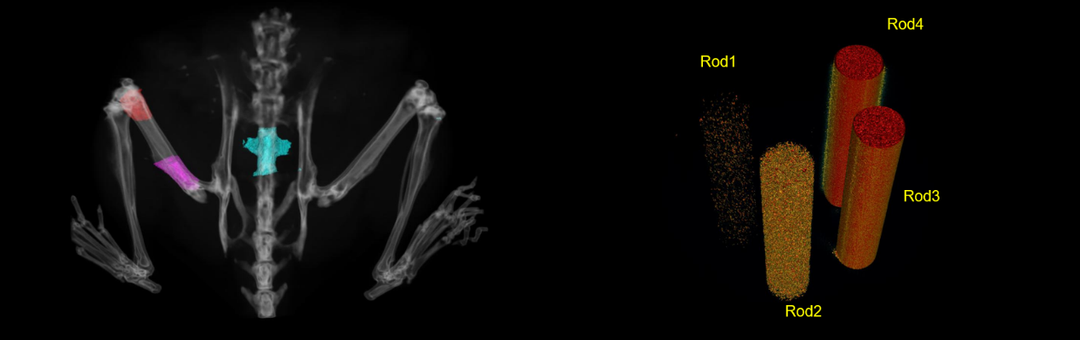

活体下,测定骨密度支持自定义区域以及长度,如红色区域股骨远端,紫色区域股骨近端及脊椎骨等。Rod1、Rod2、Rod3、Rod4分别为不同密度的羟基磷灰石。

靶向抗体药物治疗药效良好。假手术组(G3),手术组(G4),药物溶剂组(G5),药物浓度递增组(G6-G8),数据显示为平均值±SEM,并使用单因素ANOVA进行分析与G4进行比较,“in vivo BMD”与G5进行比较。